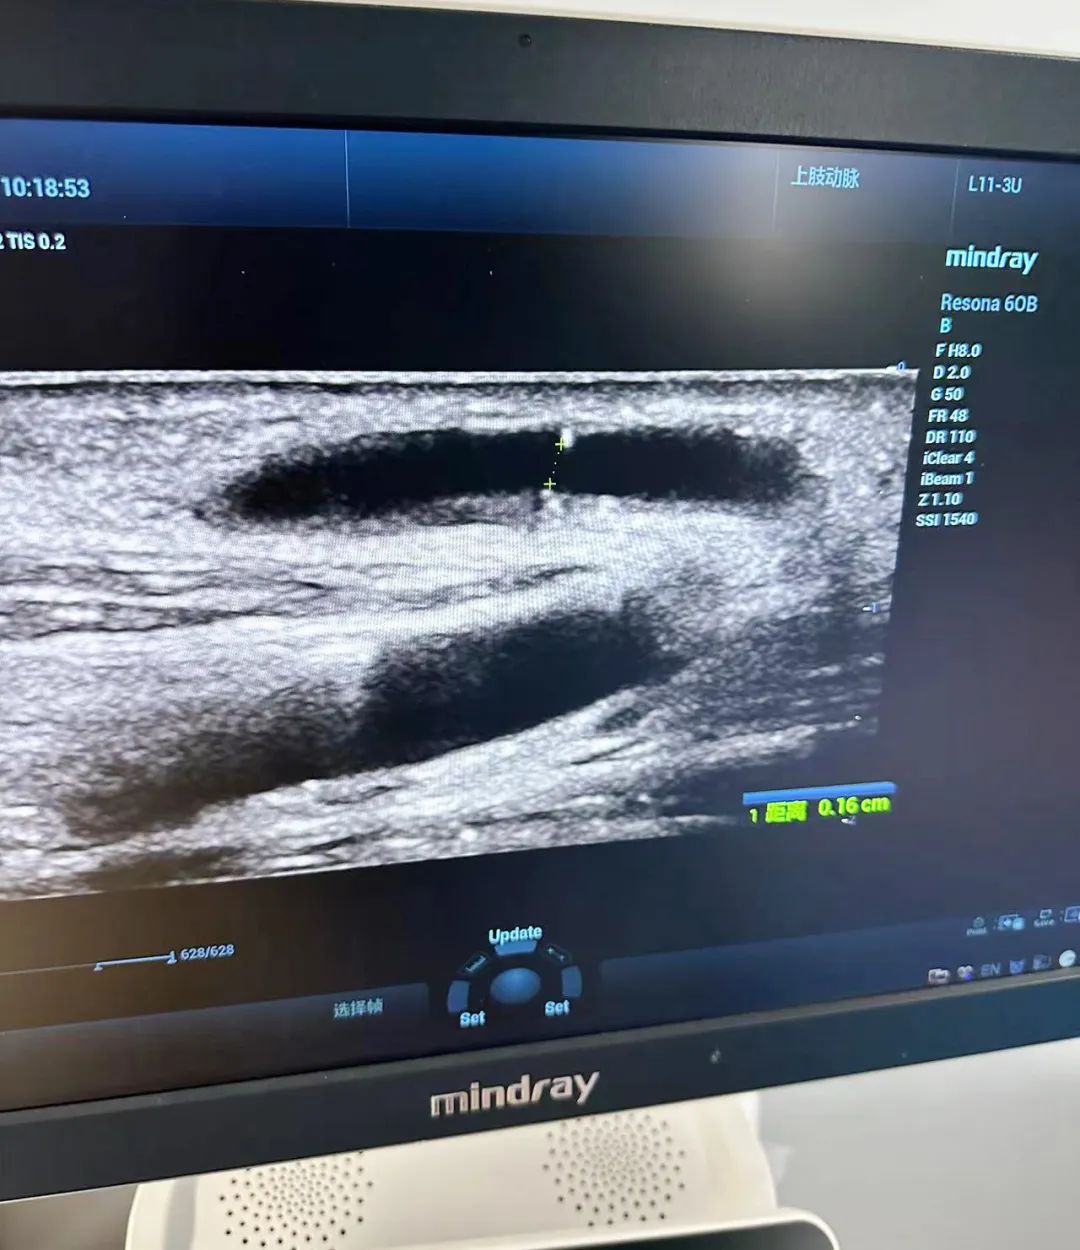

12日上午,在我院四樓遠程會診中心,李月紅教授與血透中心醫(yī)護人員共同開展一場腎友交流會活動。通過與腎病患者面對面的交流,她們更深入地了解了患者的實際需求和困擾,并就血管通路、腎性貧血、高磷血癥、血液灌流、飲食等方面提出了個性化的治療建議和指導(dǎo)。此外,李教授強調(diào),血管通路是透析患者的“生命線”。超聲對血管的評估、通路的建立、通路的管理方面發(fā)揮著重要作用。

交流會結(jié)束后,血透中心與彩超室通力合作,為多名血透患者進行了血管B超檢查。通過篩查,發(fā)現(xiàn)了一些患者血管通路出現(xiàn)問題,并及時指導(dǎo)他們進行血管通路干預(yù),以避免內(nèi)瘺的風險。同時,李教授對內(nèi)瘺評估及血流量測量,內(nèi)瘺穿刺等內(nèi)容進行細致講解,這一舉措有效提高了醫(yī)生對動靜內(nèi)瘺評估的能力,提升了護士動靜脈內(nèi)瘺彩超穿刺技術(shù)的水平,得到了醫(yī)患雙方的一致好評。